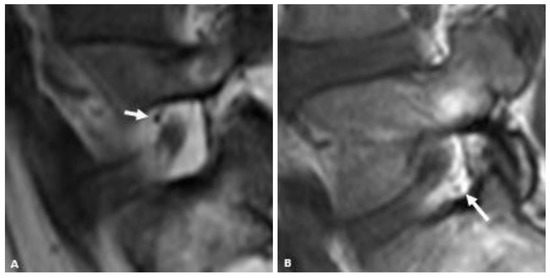

For qualitatively determining the presence and location of vessels within the neural foramen, the reviewers were instructed to use the same MRI slice that they used to judge the foraminal fat. A convincing punctate low signal intensity structure next to the nerve root (either antero-superiorly or postero-inferiorly) on the sagittal T1 sequence was considered a vessel (Figure 2). Vessels were considered present when seen but considered “Not Applicable” when not seen because in cases where there was no fat (“None”) in the neural foramen, it would not be possible to see a vessel, and because many vessels may be too small to see within the resolution limits of the MRI.

Figure 2.

Representative sagittal T1w MR images of the L5-S1 neural foramen demonstrating foraminal vessels (arrows) in the antero-superior foramen (A) and postero-inferior foramen (B).

In this study, vessels were visualized less often by MRI within the foramen in the setting of stenosis. The presence of vessels also had the lowest inter-rater reliability of all the variables recorded. The presence of vessels is important for a few reasons. For one, an embolic phenomenon related to intra-arterial injection or direct needle trauma to a dominant radiculo-medullary artery has been implicated in TFESI-related paralysis. Secondly, if the anti-inflammatory/anesthetic is administered intra-vascularly, it will not offer the local tissue effects desired from the procedure.

The inability to see vessels in the setting of stenosis is unsurprising. We identified vessels as punctate low-signal-intensity foci on T1-weighted images which may not be visible without a background of foraminal fat, as is often the case in the setting of foraminal stenosis. Vessels were more often seen in the postero-inferior foramen (16/29) than in the antero-superior foramen (10/29). This finding may simply reflect a secondary marker of the increased foraminal fat postero-inferiorly. There is a known venous plexus within the foramen, including in the postero-inferior portion of the foramen, which specifically includes the dorsal ascending vertebral vein and emissary veins, which may account for the vessels seen posteriorly by MRI [9].